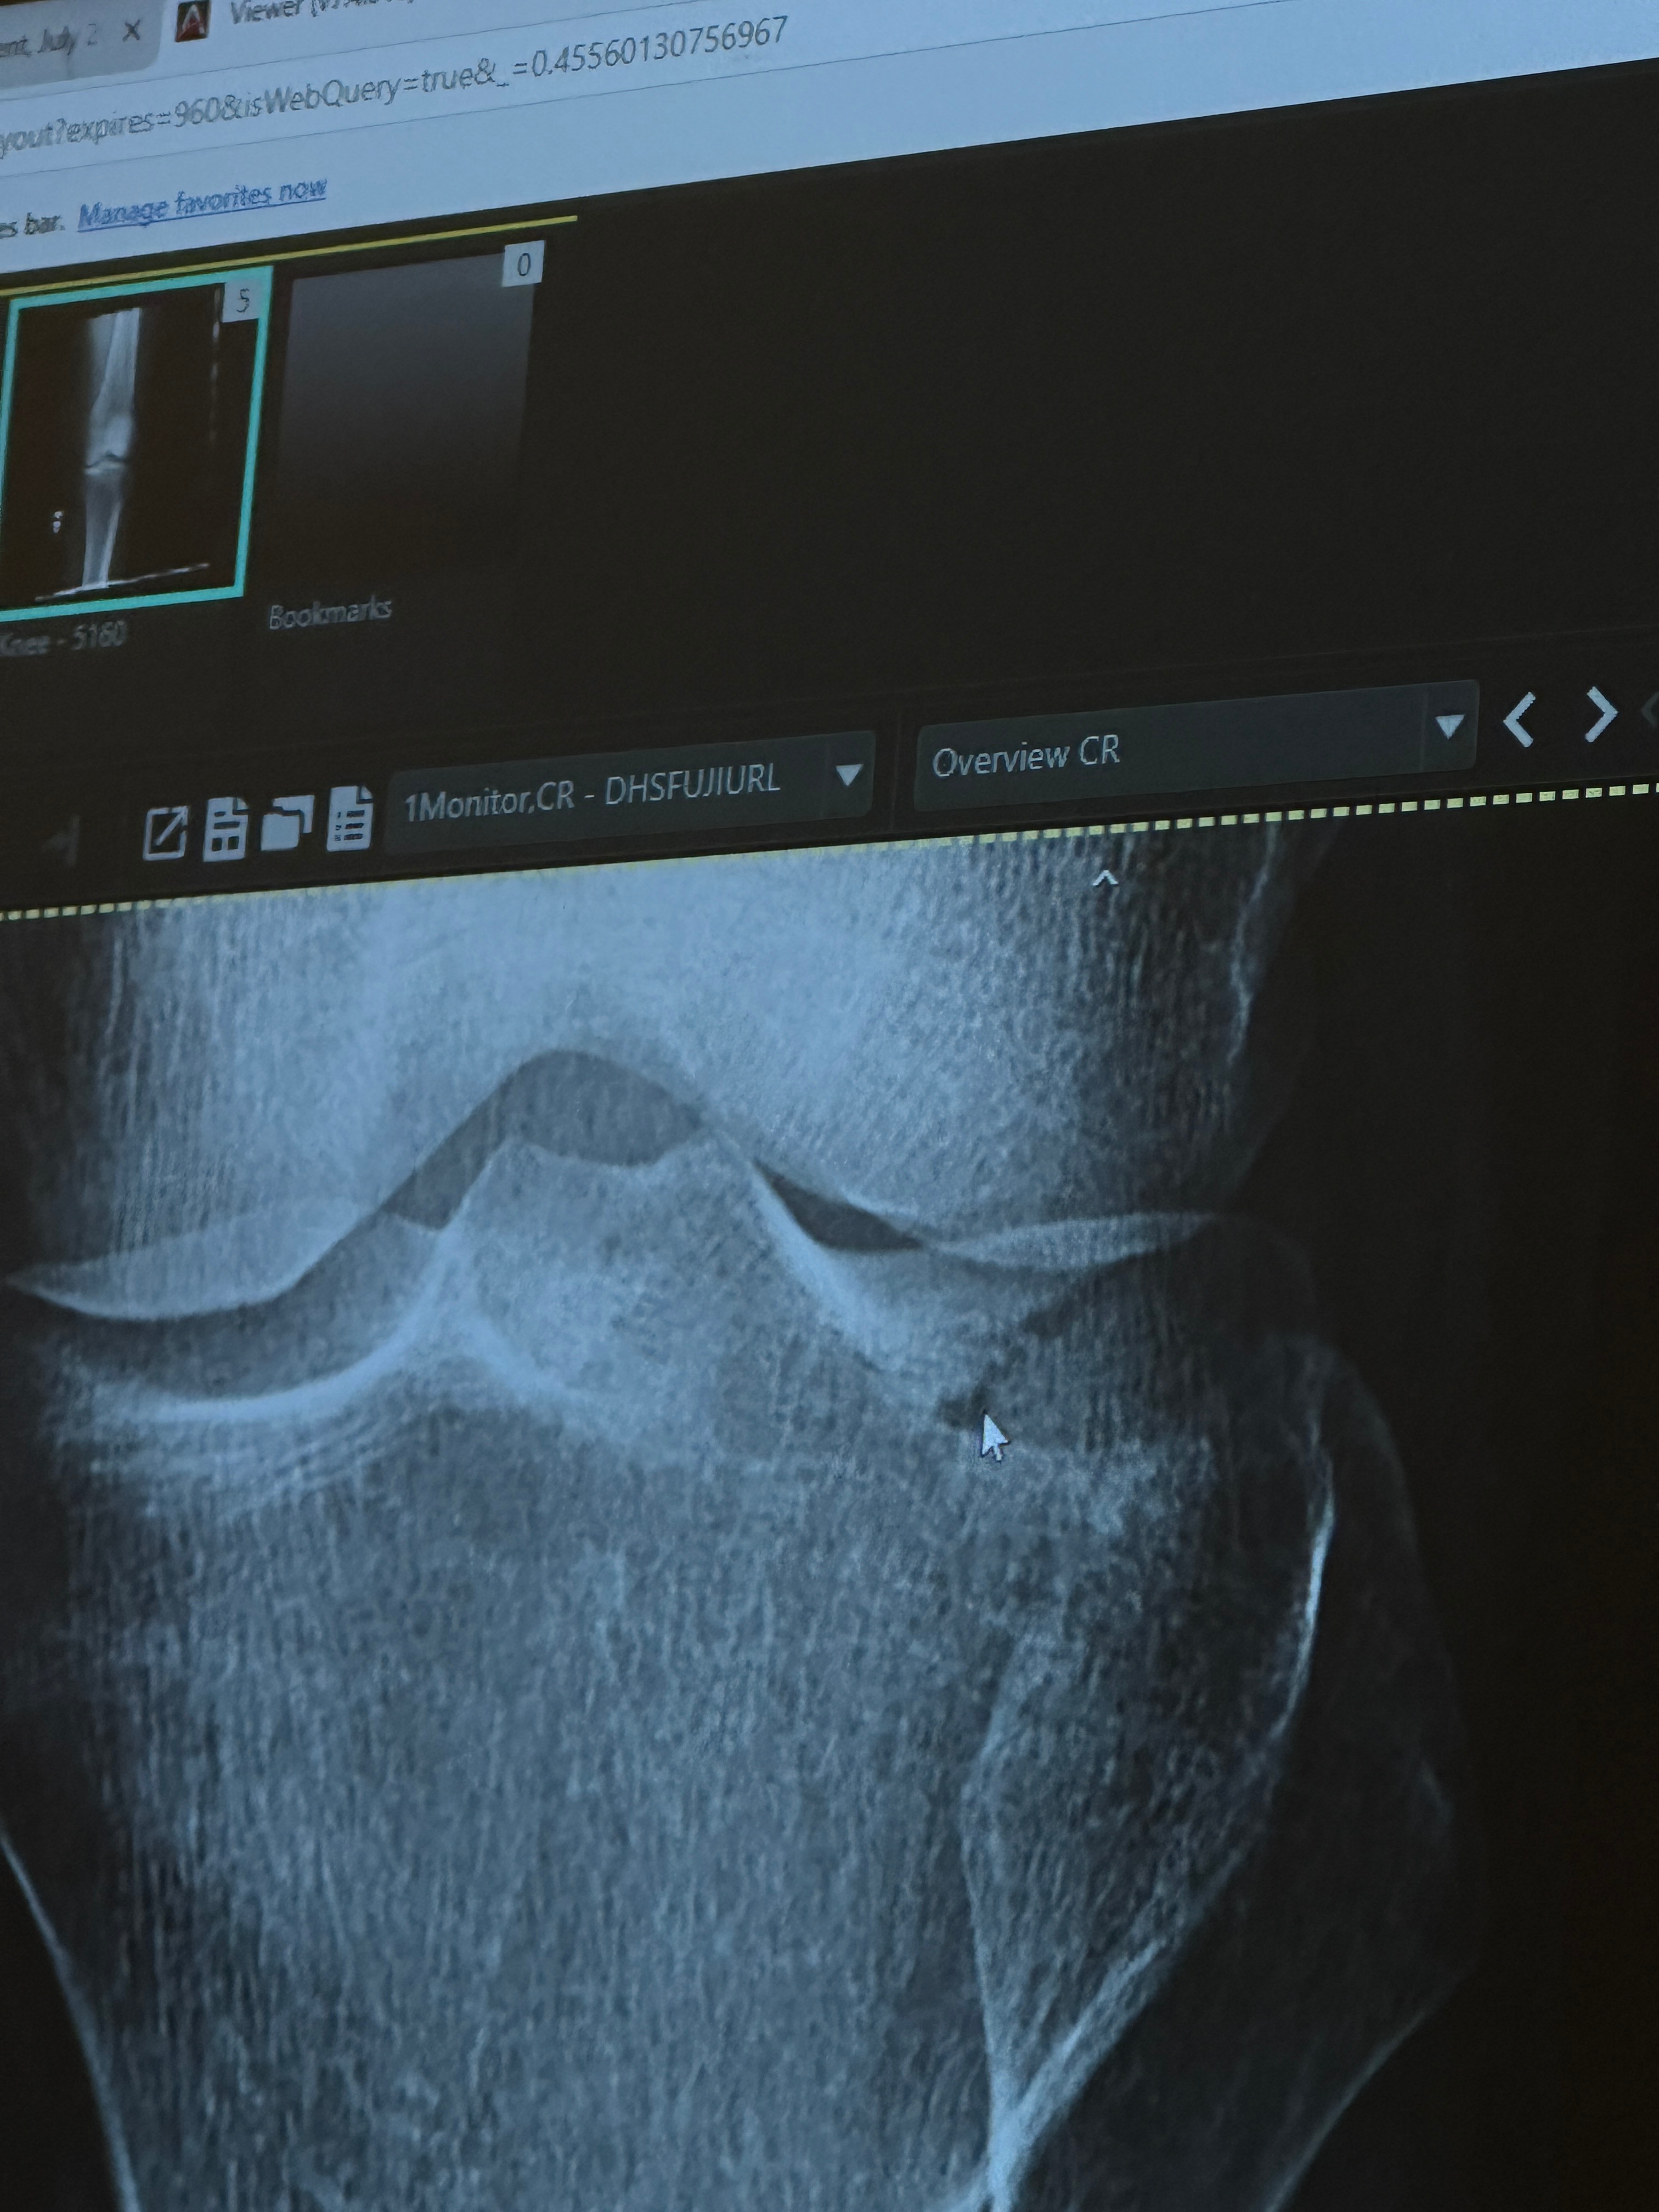

On July 28th, 2025, our beloved friend Xochi was seriously injured during Muay Thai training. She suffered a tibial plateau fracture and a torn MCL — painful injuries that require extensive recovery.